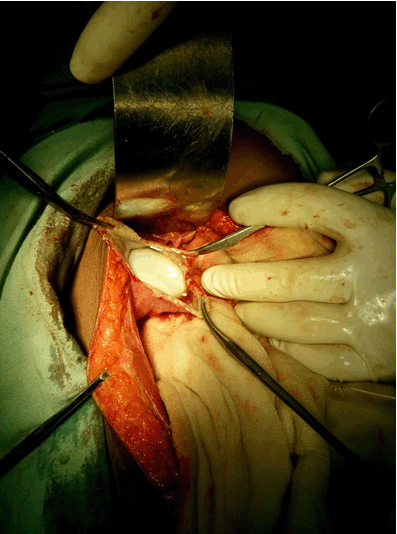

Anti-Echinococcus antibodies were not found in serum. The diagnosis of primary hydatid cyst of gallbladder was made and surgery was decided. The patient underwent right subcostal laparotomy. Intraoperatively, the gallbladder was found to be tense and hugely distended (Figure 2). The wall appeared oedematous and inflamed. After proper precaution the gallbladder wall was opened (Figure 3). A single cyst with germinal layer was delivered intact. No other cysts were found in the liver and peritoneal cavity. Cholecystectomy was performed. It permitted a total removal of the cyst without rupture. A peroperative cholangiography searching daughter cysts in the common bile duct proved unremarkable. The patient's postoperative course was uneventful and she was discharged on tenth postoperative day after stitch removal. The patient was put on albendazole (10 mg/kg) in divided doses. The histopathology confirmed the presence of hydatid cyst (Figure 4). At sixth month follow-up, the patient was well and had no recurrence of hydatid disease.

Figure 2: View of the hydatid cyst after opening the gallbladder.